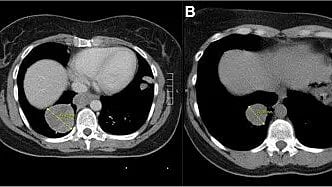

Despite advances in cancer care, treatment strategies for ampullary adenocarcinoma (AAC) remain uncertain. Its anatomic location and biological diversity lead to variable clinical behavior and outcomes. While curative pancreaticoduodenectomy is the standard therapy, recurrence affects nearly half of all patients, and the benefits of postoperative chemotherapy remain debated. Conventional prognostic markers, such as lymph node status and differentiation, fail to fully capture hidden high-risk features. Based on these challenges, it is necessary to explore clinicopathological factors that predict survival and treatment benefit in AAC, to develop more effective and individualized postoperative management.

A research team from Tianjin Medical University Cancer Institute & Hospital has provided new insights into postoperative risk stratification for AAC. The study, published (DOI: 10.20892/j.issn.2095-3941.2025.0181)1 on October 2025 in Cancer Biology & Medicine, analyzed long-term outcomes in 168 patients following curative resection. The researchers identified tumor deposits as a pivotal marker predicting who benefits from adjuvant chemotherapy, and defined the pancreatobiliary signature and blood vessel invasion as key independent prognostic features guiding clinical decision-making.

Using multivariate Cox regression and subgroup analyses, the team evaluated how clinicopathological features influence overall and progression-free survival in AAC. They found that patients with the pancreatobiliary signature (CDX2−/MUC1+) and those showing blood vessel invasion had significantly poorer outcomes, marking these as independent high-risk factors. Importantly, tumor deposits clusters of tumor cells in soft tissue disconnected from the primary lesion emerged as a crucial context-dependent biomarker. While not an independent prognostic factor overall, tumor deposit–positive patients experienced a 60% reduction in mortality risk when treated with adjuvant chemotherapy. Their median overall survival rose from 22.3 to 51.3 months. This benefit was most evident among patients with advanced-stage tumors, lymph node metastasis, or absence of blood vessel invasion. The findings suggest that identifying tumor deposits can help clinicians tailor adjuvant chemotherapy to those most likely to respond, bridging a critical evidence gap in AAC management.